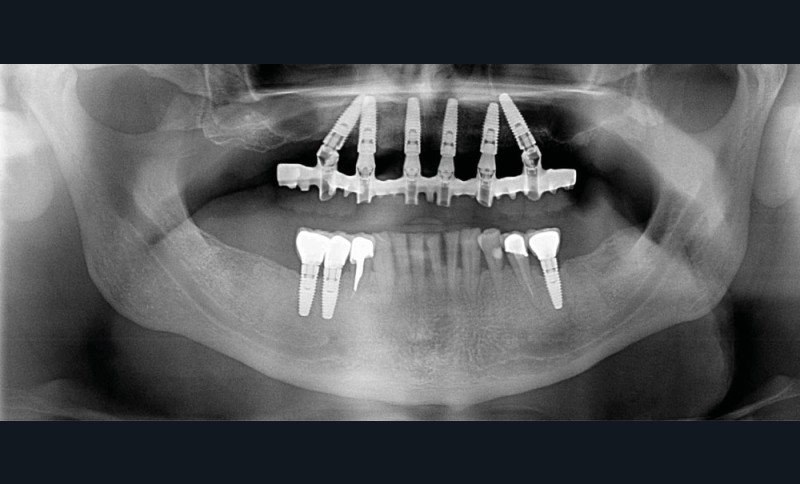

La prise en charge de ces édentements nécessite un examen complet du site implantaire et de l’environnement [16]. Les conséquences du non-remplacement rapide que nous venons d’énumérer sont à prendre en compte et à corriger pour une intégration optimale de la restauration prothétique implantaire. Ainsi, des corrections orthodontiques peuvent être nécessaires avant ou pendant la thérapeutique implantaire.

Le temps de l’ostéointégration, des versions ou migrations sont aussi possibles et le recours à des dispositifs de maintien de l’espace peut se révéler indispensable (fig. 22 et 23).